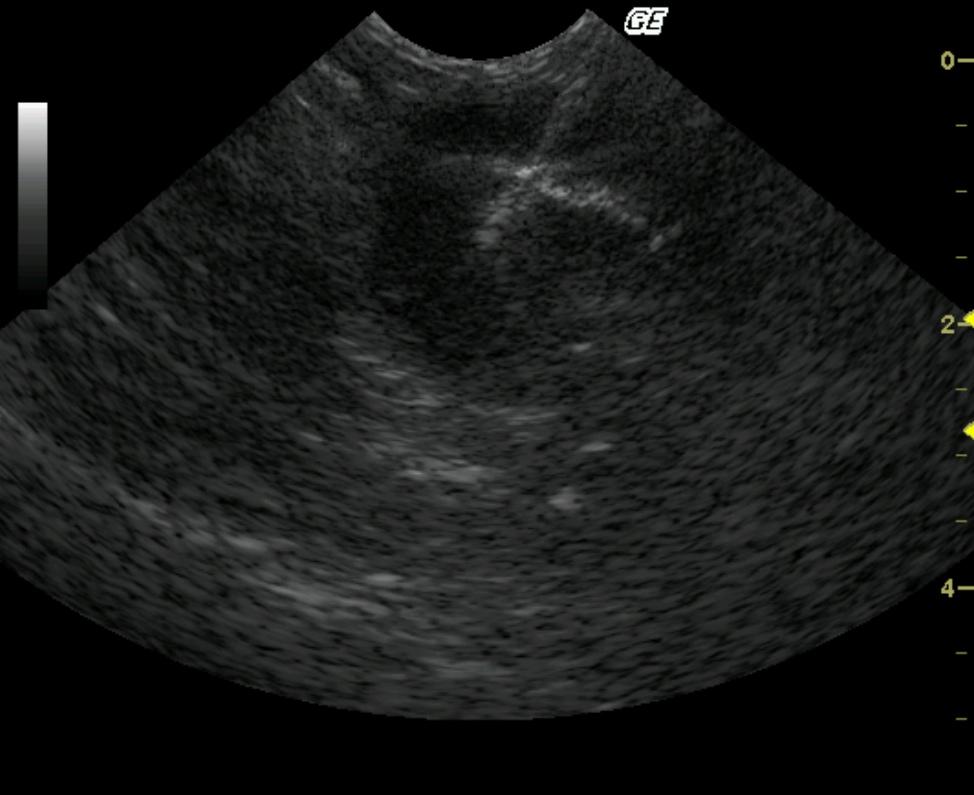

Image Interpretation

A round, intestinal wall mass was noted in the small intestine with loss of mural detail. The hyperechoic central lumen identifies the mass as intestinal in origin. The biopsy track crosses into the lumen which is not ideal as it may allow for luminal contamination of the abdominal cavity as well as the pathology sample potentially causing a septic enteritis diagnosis as opposed to a neoplastic one.